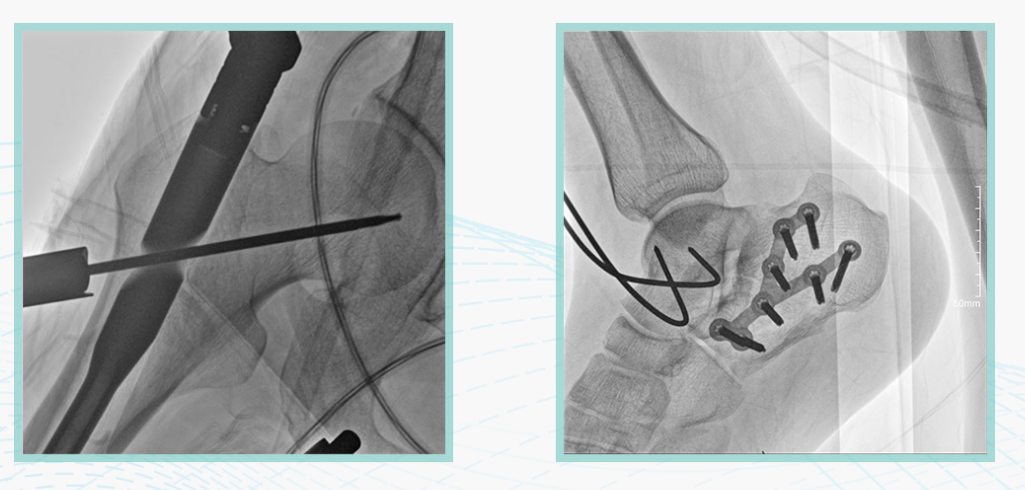

尊龙凯时人生就是博科技悦画移动C臂X线摄影系统,采用了业内技术最尖端的CMOS探测器。基于性能优异的针状CSI闪烁体涂层和高灵敏度的CMOS感光芯片,悦画可以实现在超低X线剂量条件下实现高清晰影像成像,相较于一般的影增移动C臂和平板C臂,动态范围更高,影像的层次感和对比度更好。

在产品的性能参数设计上,悦画的像素可达到200万,空间分辨率可达到3.2线对,采用16bit的影像灰度,悦画在影像后处理上,通过SPI金字塔图像算法,支持摄影、脉冲透视影像、连续透视等多种模式下的影像采集,动态透视影像视频支持保存与回放。双大屏的设计,透视影像支持三档放大,保证临床影像读取的便利。

悦画在影像的伪影处理上,也积累多项图像处理专利技术。通过对植入物的精准识别,悦画能够精准祛除植入物伪影与运动伪影,保证高质量的影像输出,无论是影像的对比度、分辨率(清晰度)相较于市面上的移动C臂产品都更胜一筹。